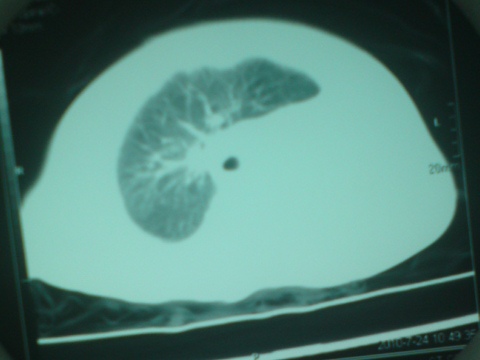

以下是引用liaoqiang在2010-7-26 13:10:00的发言:[br]左侧主支气管未显示,左肺体积明显缩小。右肺体积大。肋间隙不窄。考虑左肺不发育伴右肺代偿性肺气肿、纵隔疝。

以下是引用江广1996在2010-7-26 10:34:00的发言:[br]因为胸廓对称,肋间隙基本正常,故考虑为先天性左肺不发育。[br]如为异物,也会有临床病史。另,这与双胞胎有什么关系,另一个情况怎样?有无检查过?